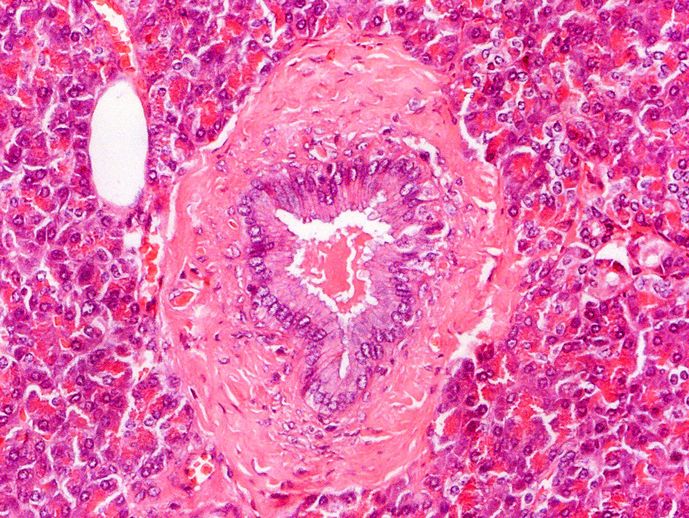

Small blood vessel vs Duct

Blood vessel are lined with endothelium which consists of squamous cells. This artery still contains red blood cells in the lumen. This is not always the case. An elastic lamina is visible. Spindle-shaped nuclei of smooth muscle fibres are clearly visible in the wall of the artery. The artery is surrounded by adventitia.

Arround the artery are a few small veins and several nerve fibres.

The duct is lined with a low columnar epithelium. The wall of the duct consists of connective tissue. The duct lies embedded in the surrounding exocrine pancreas.